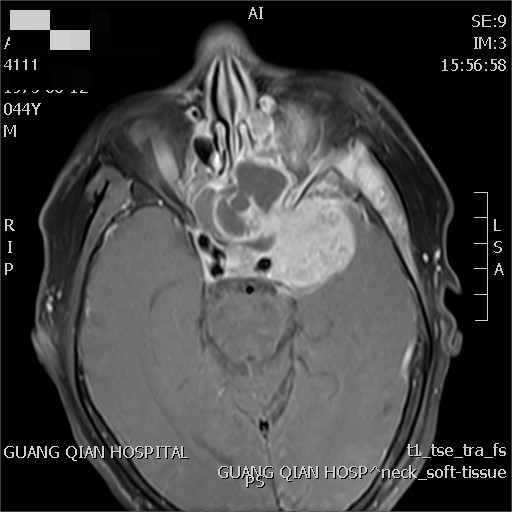

治療前后對(duì)比

林先生,因頭痛2年,近期前來(lái)我院診療,診斷鼻咽癌IV期。經(jīng)過(guò)姜教授指導(dǎo)放化療后,腫瘤基本消失。